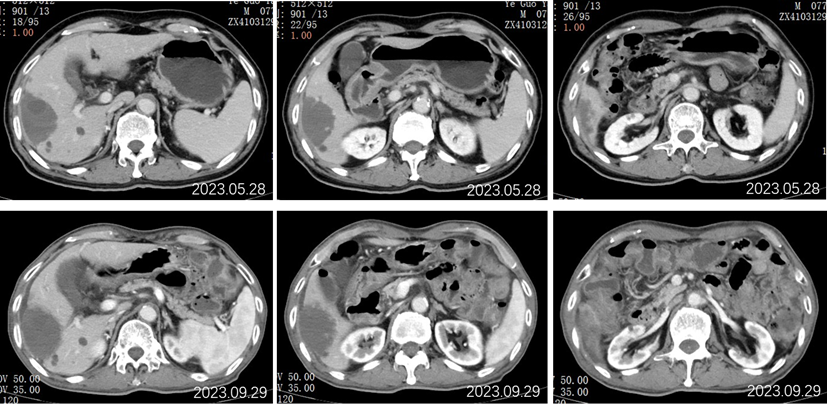

2023.5.28胸部CT平扫:对比2022-11-25片:1.两肺散在多发炎症,较前相仿,VP-RADS 2类;2.两肺多发小结节、类结节影,转移瘤考虑,较前相仿;3.左侧第5后肋骨质异常,相仿。男性乳腺发育。

2023.5.28腹部CT增强:肝胆管细胞癌治疗后复查:对比2022-11-25日:1、肝右叶多发占位,较前相仿;2、肝内及双肾多发小囊肿,肝S2小血管瘤,大致相仿;3、慢性胆囊炎改变;胆囊内点状结石未见显示;4、肝内钙化灶;前列腺钙化灶。

2023.09.29胸部CT平扫:对比2023-05-28片:1.两肺多发小结节、类结节影,较前增多增大,转移瘤考虑。2.两肺散在多发炎症,部分较前吸收;3.左侧第5后肋骨质异常,相仿;4.右侧胸腔少量积液。男性乳腺发育。

2023.09.29腹部增强CT:肝胆管细胞癌治疗后复查:对比2023-05-28日:1、肝右叶多发占位,较前大致相仿;2、肝内及双肾多发小囊肿,肝S2小血管瘤,大致相仿;3、慢性胆囊炎改变;胆囊周围渗出,较前稍增多;4、肝内钙化灶;前列腺钙化灶;新见盆腔少量积液。